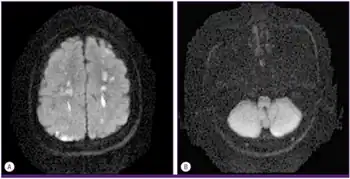

The two more severe forms of the disease are visceral toxocariasis and ocular toxocariasis. Visceral toxocariasis typically occurs in children, but can infect persons of any age. Signs and symptoms can include fever, wheezing, hepatomegaly, abdominal pain, anorexia, or skin reaction. Rarely, the migrating larvae can cause eosinophilic meningitis or encephalitis, myelitis, optic neuritis, radiculitis, cranial nerve palsy, or myocarditis. In lab findings, there is almost always a marked peripheral eosinophilia and often, anemia and a hypergammaglobulinemia.[8]

Ocular toxocariasis typically occurs in 5 to 10-year-olds resulting in significant damage to the eye.[9] Usually only one eye is affected, and manifestations can include strabismus, decreased vision, and leukocoria. Eye exam may show a subretinal granulomatous mass or posterior pole granuloma.[8] Even in relatively healthy people, the roundworm larvae infect organs such as the liver, lungs, eyes or brain and cause severe symptoms, such as:[10]